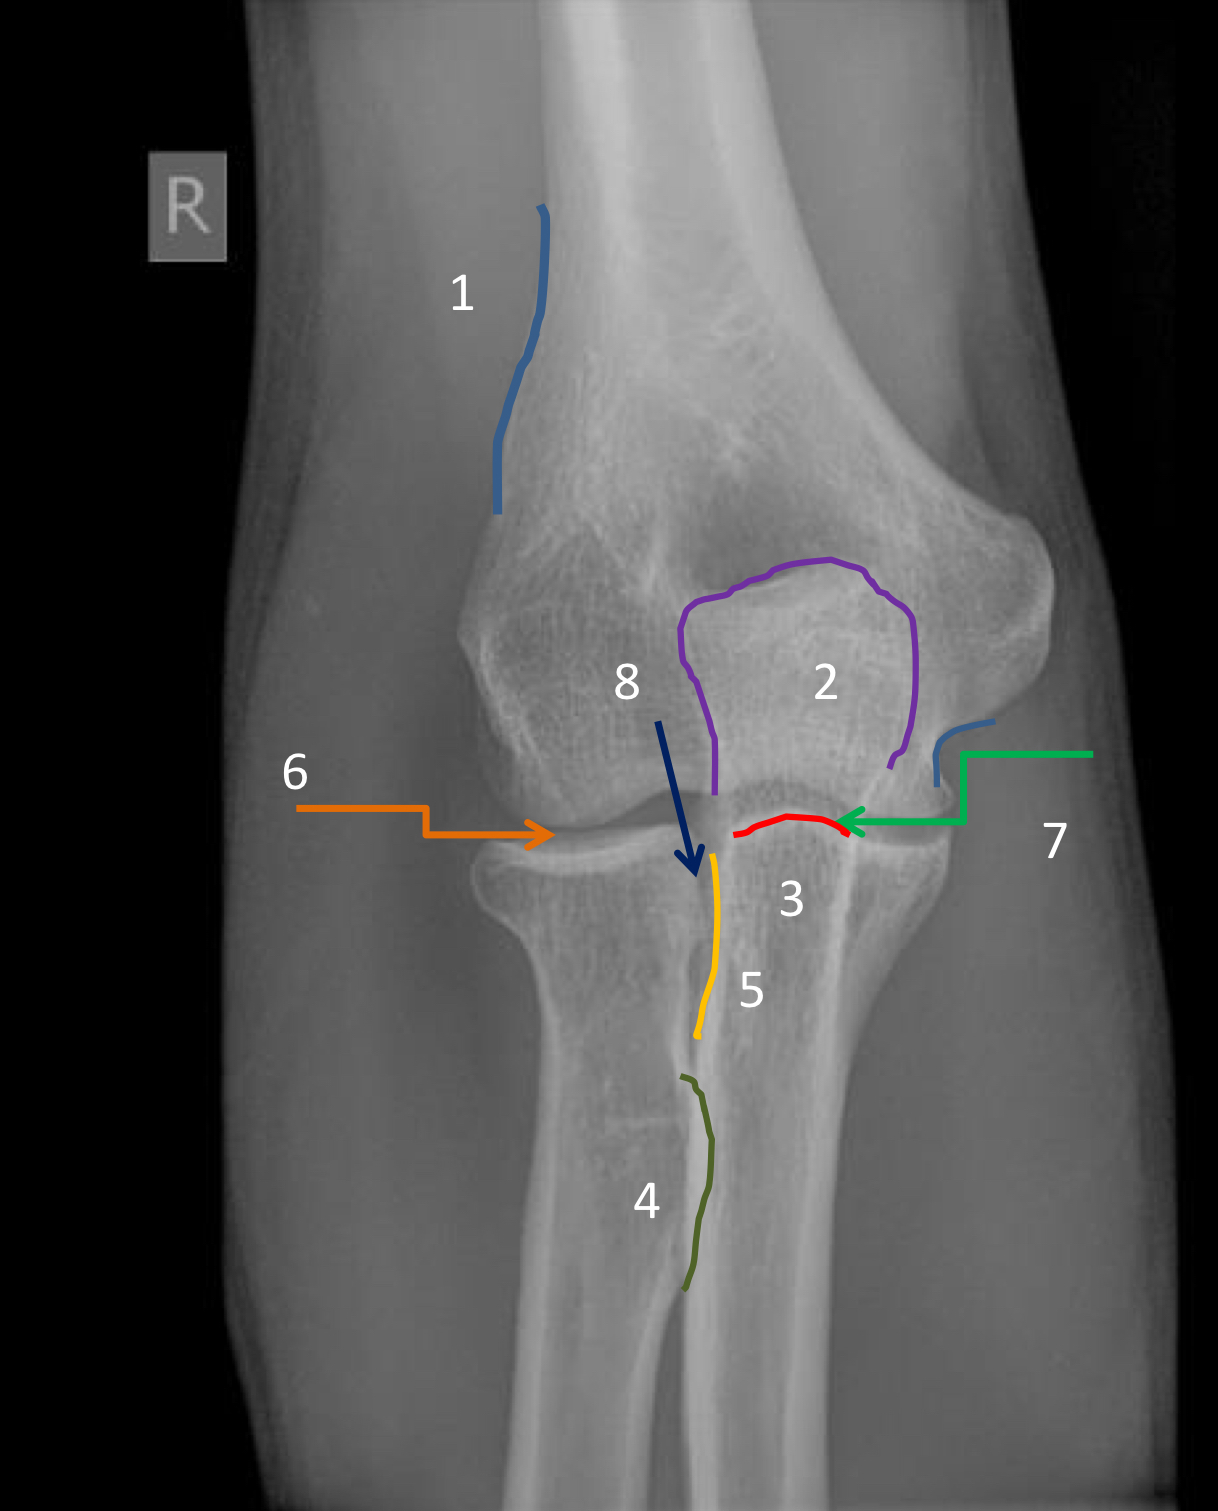

1?

lateral supracondylar ridge

2?

olecranon process

3?

coronoid process

4?

radial tuberosity

5?

radial notch of the ulna